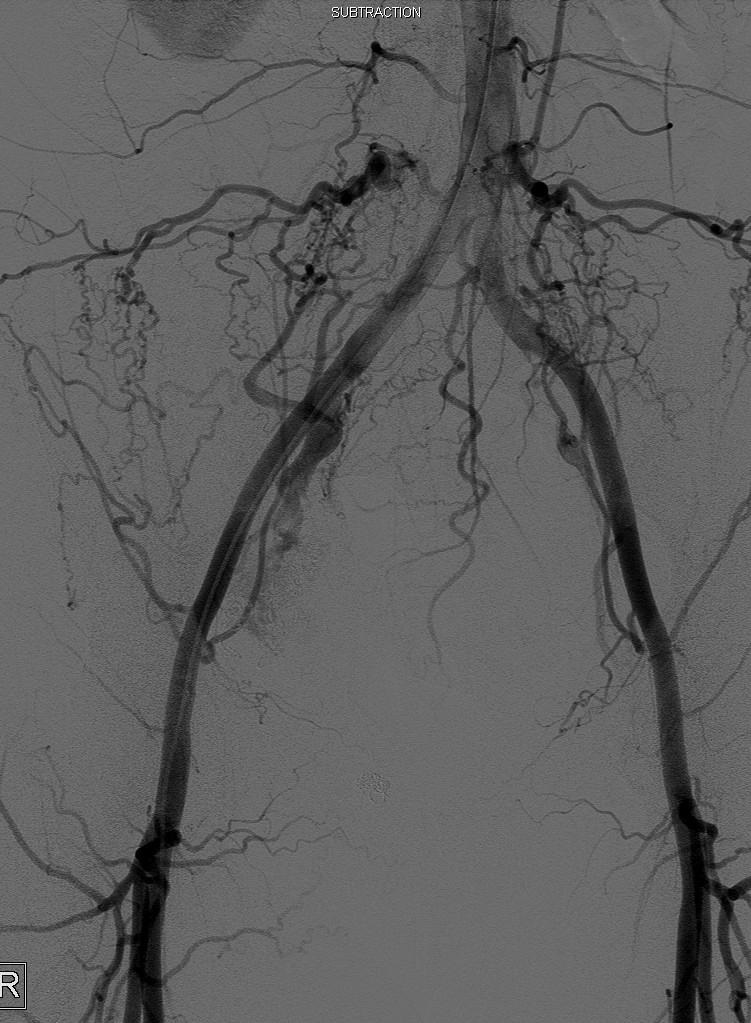

盆腔动脉非选择动脉造影

|

非选择血管造影(Non-selective arteriograms) |

双髂动脉结扎后 |

通常难以描述动静脉畸形交通的解剖关系 |

Often difficult to assess anatomy of arteriovenous communications |

双髂动脉闭塞,但不明确动静脉间交通解剖类型 |